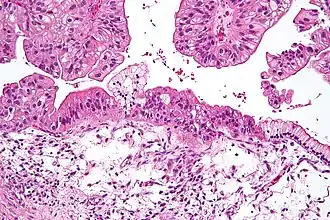

![]() Cistoadenocarcinoma mucinoso de ovario visto bajo el microscopio, tinición HE. | ||

El cistoadenocarcinoma es un tipo de cáncer o tumor maligno que se desarrolla a partir de tejido glandular y puede originarse en diferentes partes del organismo, principalmente ovario y páncreas, más raramente en apéndice, tiroides y glándulas salivares. El nombre proviene de que se forman pequeñas vesículas o quistes llenas de líquido y tapizadas por células tumorales. Existen dos variedades, el cistadenocarcinoma seroso en el que los quistes están llenos de un líquido seroso claro, y el cistadenocarcinoma mucinoso en el que la sustancia de los quistes es de consistencia gelatinosa. La variedad benigna de este tumor se denomina cistoadenoma. [1][2]